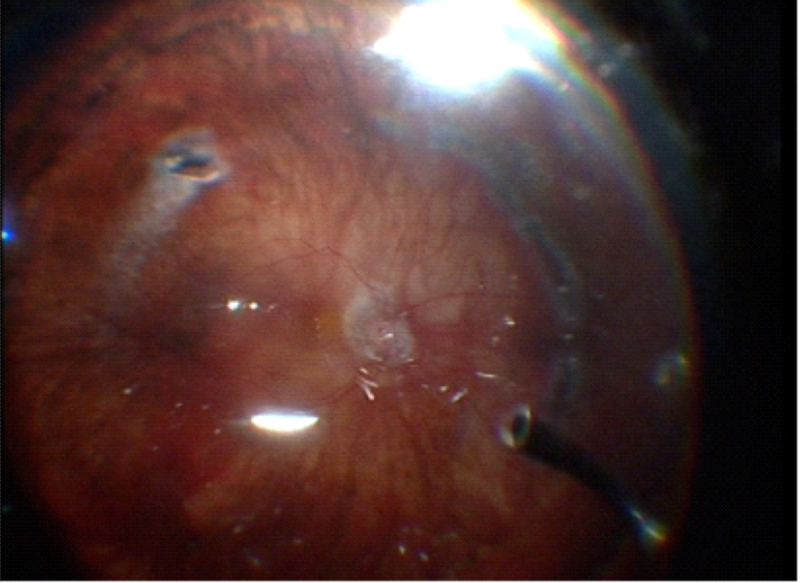

Para obtener la identificación del gel incarcerado en las esclerotomías se realiza el depósito bajo depresión escleral de la esclerotomía permitiendo la identificación completa de las fibras de gel (

Figura 2,

Figura 3, Figura 4 y

Figura 5).

Figuras 3 y 4. Disección de Hialoides posterior ayudado por Triamcilonona y Perfluorocarbono (PFCL) en desprendimiento de retina.

Figura 5. Cavidad vítrea bajo aire, donde no se objetivan restos de PFCL, ni TA.